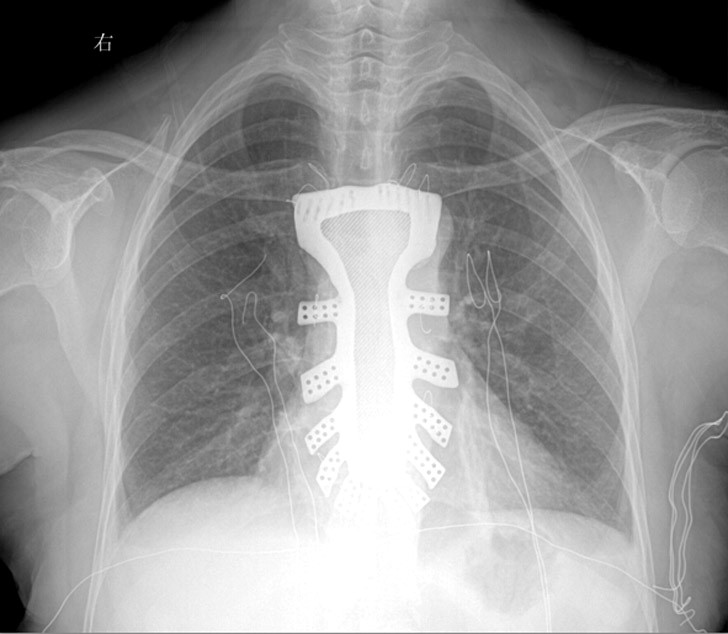

首个成功植入的3D打印胸骨

6月22日,该团队收到钛合金植入体之后马上准备手术,这张图片是植入后的情形。顾女士已经恢复,且无任何并发症,我们祝福她。